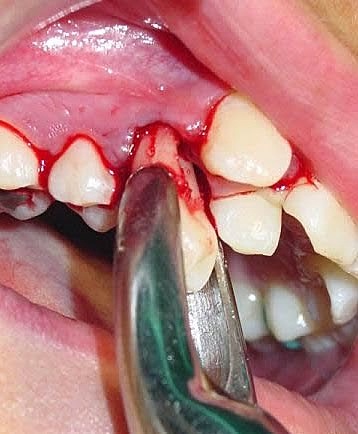

• Curetaje cerrado superior

Curetaje cerrado superior

En los cuadrantes 1 y 2 se realizó curetaje cerrado con la finalidad de eliminar las bolsas periodontales mayores de 3 milímetros. Durantes este procedimiento se anestesió con 4 cartuchos de lidocaína con epinefrina. El sangrado fue moderado y no se presentó ninguna complicación quirúrgica.